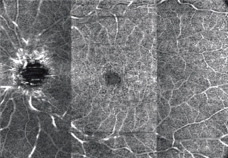

パノラマ自動合成機能

12×9mmの撮影範囲内で2種(3/4.5mm)のパノラマ合成を自動でおこなうことが可能です。

スキャン位置は順次移動するため、固視位置を変更することなく撮影できます。

任意設定により5種類(初期設定:網膜全層、表層、深層、外層、脈絡膜)のパノラマが同時に自動合成できます。

網膜全層 HD4 4.5×4.5mm 6枚 パノラマ |

網膜表層 |

網膜深層 |

網膜外層 |

脈絡膜 |